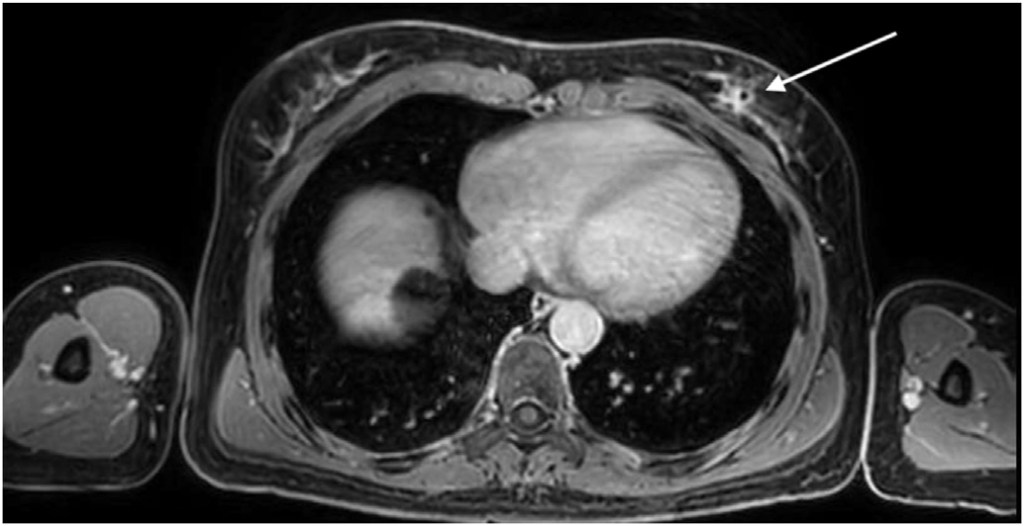

Three breast surface markers (BSM) were applied on the patient’s breasts (infra-mammary sulcus) along with a 10 cm fiducial marker below the xiphoid process (Fig. 1). These reference points were annotated with a black permanent marker at the patient’s skin. A 3D surface scan of the patient was performed in the supine position with arms at 90 degrees (Fig. 1), capturing the size and shape of both breasts and torso using a Go!Scan 3D handheld by CreaformTM. After 3D surface scan, fish-oil capsules were fixed on the three BSM marks for MRI acquisition. A contrast-enhanced MRI was performed with the patient in prone position and markers in place. The institutional breast MRI acquisition protocol was modified to include a final 5-min Dixon sequence with the phased array torso MRI coil and the patient in the supine position with arms along the body (Fig. 2).